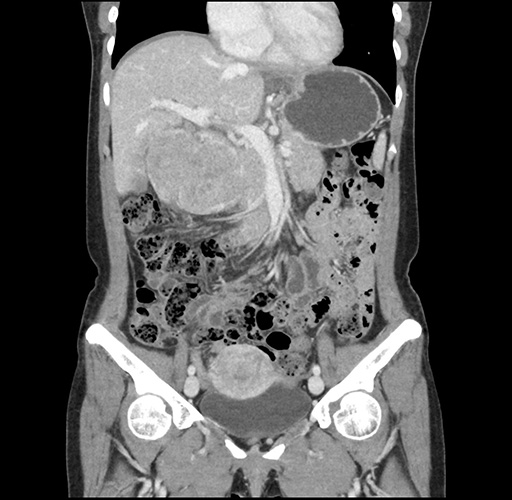

Imaging Analysis

Look through the patient's CT scan to identify any areas of concern for the necessary procedure.

Based on your CT findings, which issue(s) would give reason for "planned slowing down moment(s)" in this case?

Considering a standard left lateral sectionectomy procedure, what step(s) of the operation would you do differently in this case ?